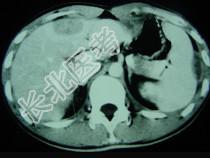

- 单项选择题男,35岁, 病人低热、消瘦、乏力,左右季肋区疼痛, CT扫描如图所示,请选择最佳诊断 ( )

A、肝海绵状血管瘤、腹腔脓肿

B、肝脏及腹腔转移瘤

C、肝脓肿、腹腔脓肿

D、肝癌、腹腔转移

E、肝结核、腹腔结核